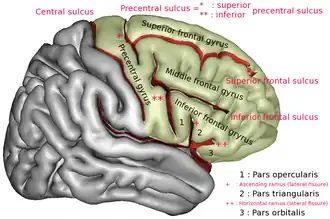

Orbital part of inferior frontal gyrus labelled 3. | |

Lateral surface of cerebral cortex | |

The orbital part of inferior frontal gyrus also known as the pars orbitalis is the orbital part of the inferior frontal gyrus.[1]

In humans, this region is bordered by the triangular part of the inferior frontal gyrus (pars triangularis) and, surrounding the anterior horizontal limb of the lateral sulcus, a portion of the opercular part of inferior frontal gyrus (pars opercularis). Bounded caudally by the anterior ascending limb of the lateral sulcus, it borders on the insula in the depth of the lateral sulcus. It is bordered anteriorly/inferiorly by the lateral orbital sulcus.[2][3]

Lateral view of a human brain showing main gyri labeled.

Lateral view of a human brain showing main gyri labeled. -